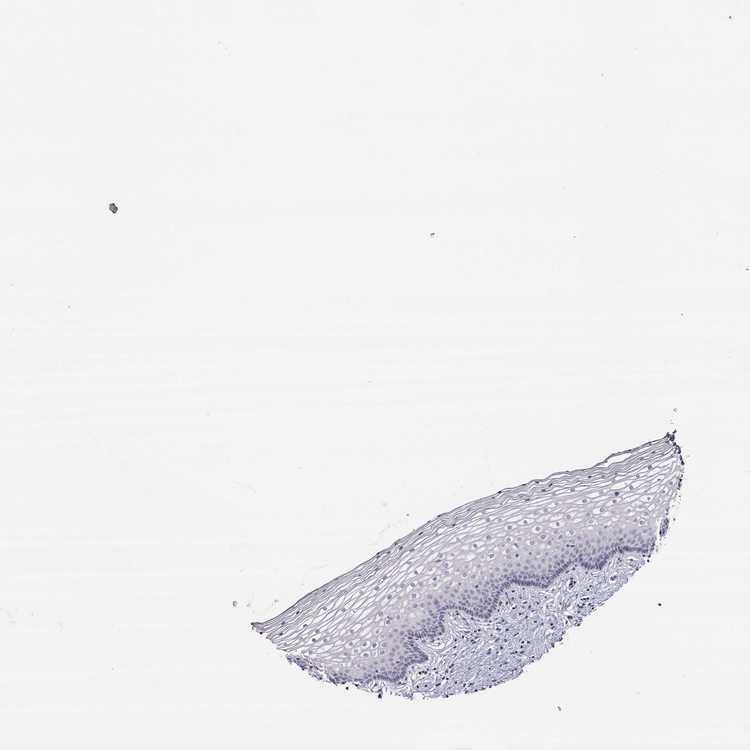

VAGINA - Antibody stainingi

Antibody staining in the annotated cell types in the current human tissue is reported as not detected, low, medium, or high, based on conventional immunohistochemistry profiling in selected tissues. This score is based on the combination of the staining intensity and fraction of stained cells.

Each image is clickable and will lead to virtual microscopy that enables deeper exploration of all samples and also displays staining intensity scores, fraction scores and subcellular localization as well as patient and tissue information for each sample.

Antibody HPA007305Antibody HPA007306Antibody CAB000106

Squamous epithelial cells Not detectedNot detectedNot detected